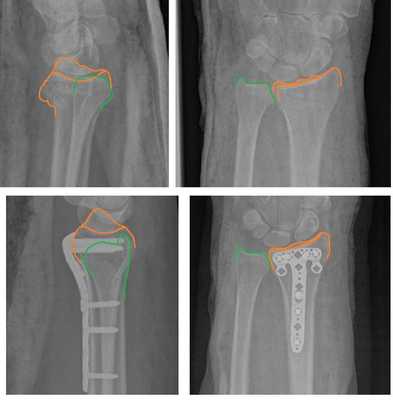

На представленной рентгенограмме не тренированный глаз может вообще не увидеть перелома, хотя врач травматолог и квалифицированный рентгенолог заметят насколько «просела» суставная поверхность лучевой кости, и отметят, что она развёрнута в тыльную сторону на 10 градусов (в норме она должна смотреть в ладонную сторону). Если присмотреться повнимательнее становятся видны линии перелома.

Намного более отчётливо степень нестабильности этих костных фрагментов видна под ЭОП-ом при выполнении функциональных проб. При тыльном сгибании определяется значительное количество мелких фрагментов тыльной кортикальной пластинки и внутрисуставной, оскольчатый характер перелома.

По этой причине в нашей клинике мы предпочитаем лечить такие типы переломов оперативно. Для фиксации данного типа повреждений предпочтительно использовать пластины с угловой стабильностью с дистальным расположением винтов, которые можно ввести субхондрально, ближе к суставной поверхности. В своей практике мы используем пластины фирмы Synthes - 2.4mm Variable Angle LCP® Volar Rim Distal Radius System.

Такой тип фиксации позволяет добиться стабилизации перелома, отказаться от гипсовой иммобилизации и начать раннюю разработку движений в лучезапястном суставе, что в конечном счёте приводит к отличным функциональным результатам. Оперативное вмешательство целесообразно проводить непосредственно в день травмы, до нарастания отёка, оптимально - в первые 6 часов после травмы.